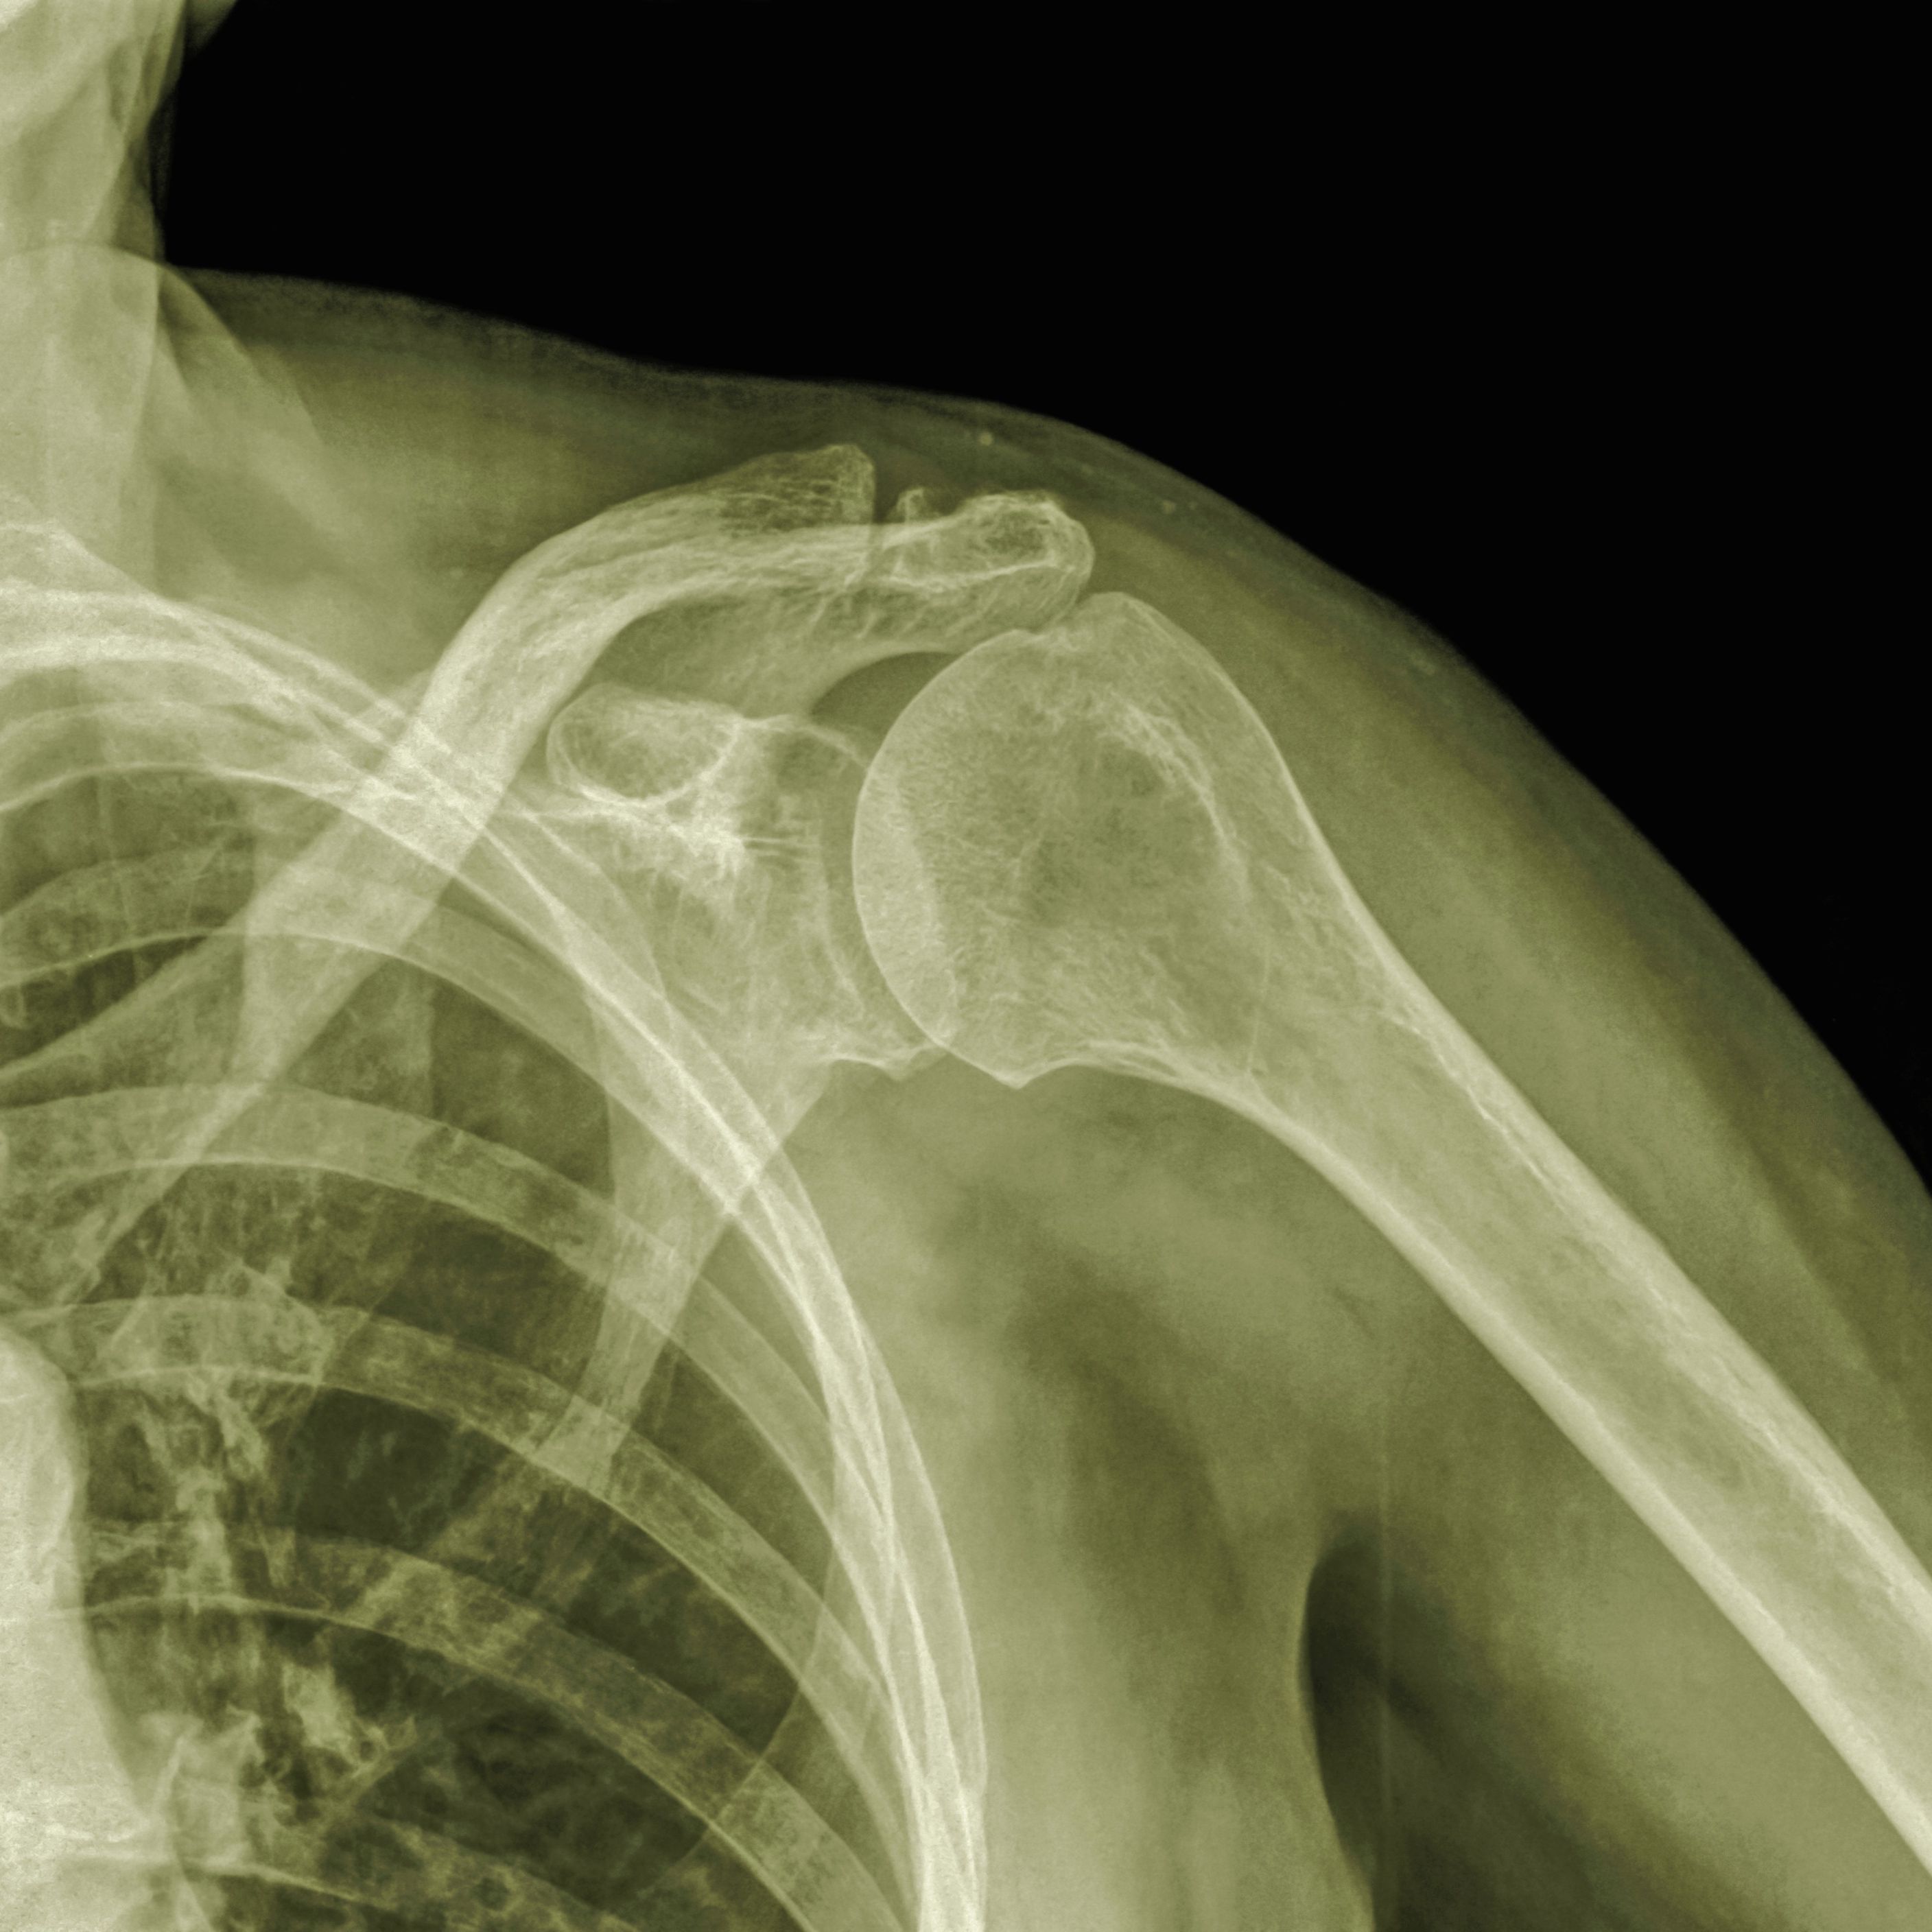

AC joint injuries

The AC joint is where the acromion (a part of the shoulder blade) connects to the clavicle (collar bone) at the top of the shoulder. This joint helps maintain the position of the shoulder and is very important for shoulder control, motion, and strength. The joint is stabilized by a capsule and ligaments, and injury occurs when these structures are damaged. When the capsule and ligaments are injured, the joint can become unstable and painful, and shoulder function can be affected. This type of injury is referred to as an “AC joint sprain” or a “separation.” These injuries typically occur after a sudden fall onto the shoulder. The AC joint is also a common place that arthritis develops, which can become painful. This is usually the result of years of degeneration or “wear and tear” of the joint and is common in weight lifters and laborers.AC Joint Arthritis Surgery is performed by orthopedician.